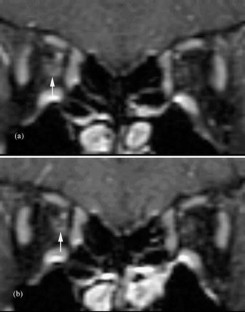

Optic nerve sheath dilatation or gadolinium-enhancement on magnetic resonance imaging in acute optic neuritis have been previously reported but have been thought to be rare occurrences. This study recruited 33 patients with acute unilateral optic neuritis. All had their optic nerves imaged with fat-saturated fast spin-echo (FSE) imaging, and 28 had imaging before and after triple-dose gadolinium-enhanced fat-saturated T1-weighted imaging. Follow-up imaging was performed on 20 patients (15 following gadolinium). A dilated subarachnoid space at the anterior end of the symptomatic optic nerve on FSE imaging was seen in 15/33 cases. In three of these cases, dilatation was visible on short-term follow-up. Optic nerve sheath enhancement was seen in 21/28 cases acutely: seven at the anterior end of the lesion only, five at the posterior end only and nine at both ends. Optic sheath enhancement was seen in 13 patients on follow-up. This study suggests that optic nerve sheath dilatation on FSE images and optic nerve sheath enhancement on triple-dose gadolinium-enhanced images are common findings in acute optic neuritis. Optic nerve sheath dilatation may be due to inflammation of the optic nerve, with its associated swelling, interrupting the communication between the subarachnoid space of the diseased optic nerve and the chiasmal cistern. Optic nerve sheath enhancement suggests that meningeal inflammation occurs in optic neuritis, in agreement with pathological studies of both optic neuritis and multiple sclerosis.